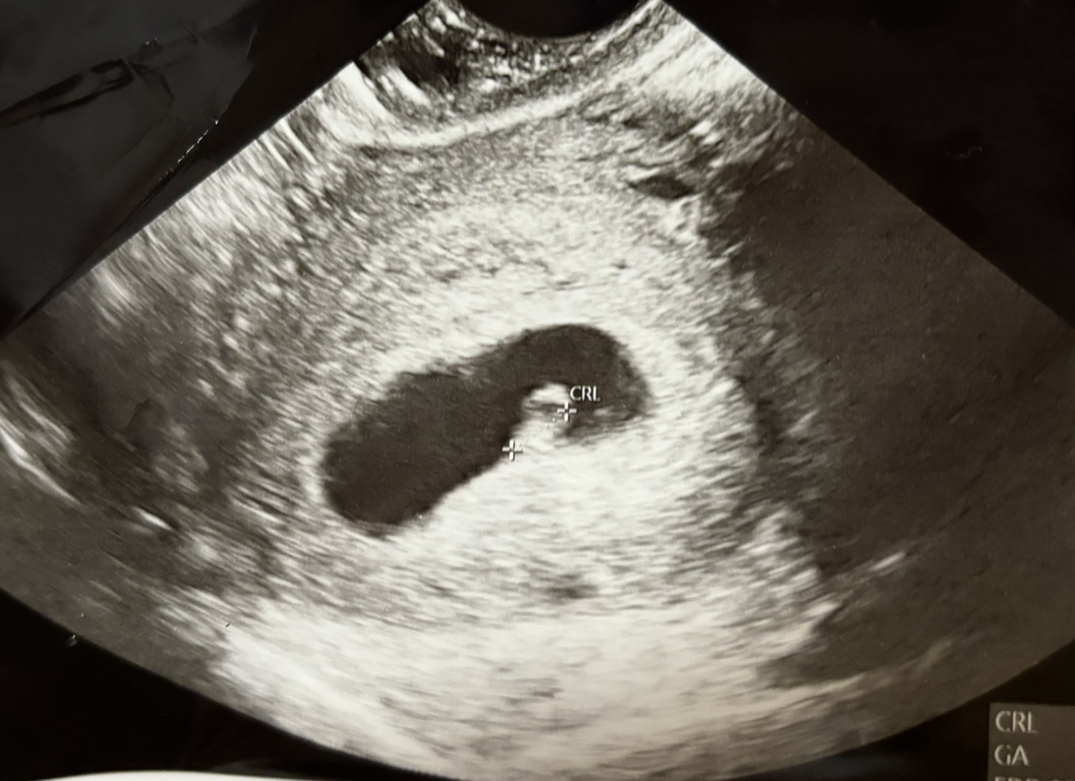

약 2주 전 테스트기/ 학교 병원에서 임신을 확인했다. 학교 병원에서는 테스트 외에는 해줄 수 있는 게 없다고 해서, Referral을 받고 심장 소리가 확실히 들릴 때까지 기다렸다 오늘 처음 진짜 산부인과에 갔다.

시스템은 비슷한 듯 달랐다. 한국은 초음파를 병원에서 같이 보는데 여기서는 세부 초음파는 산부인과와 협업을 맺은 다른 파트너사에 별도로 예약을 잡아서 해야 한다고 했다. 맨해튼에서 가장 큰 병원인데도 그랬다. 임신 기간 내내 산부인과와 그곳을 왔다 갔다 해야 하는 모양이었다.